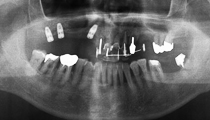

サイナスリフト実施7ヶ月後、インプラント埋入を行いました。